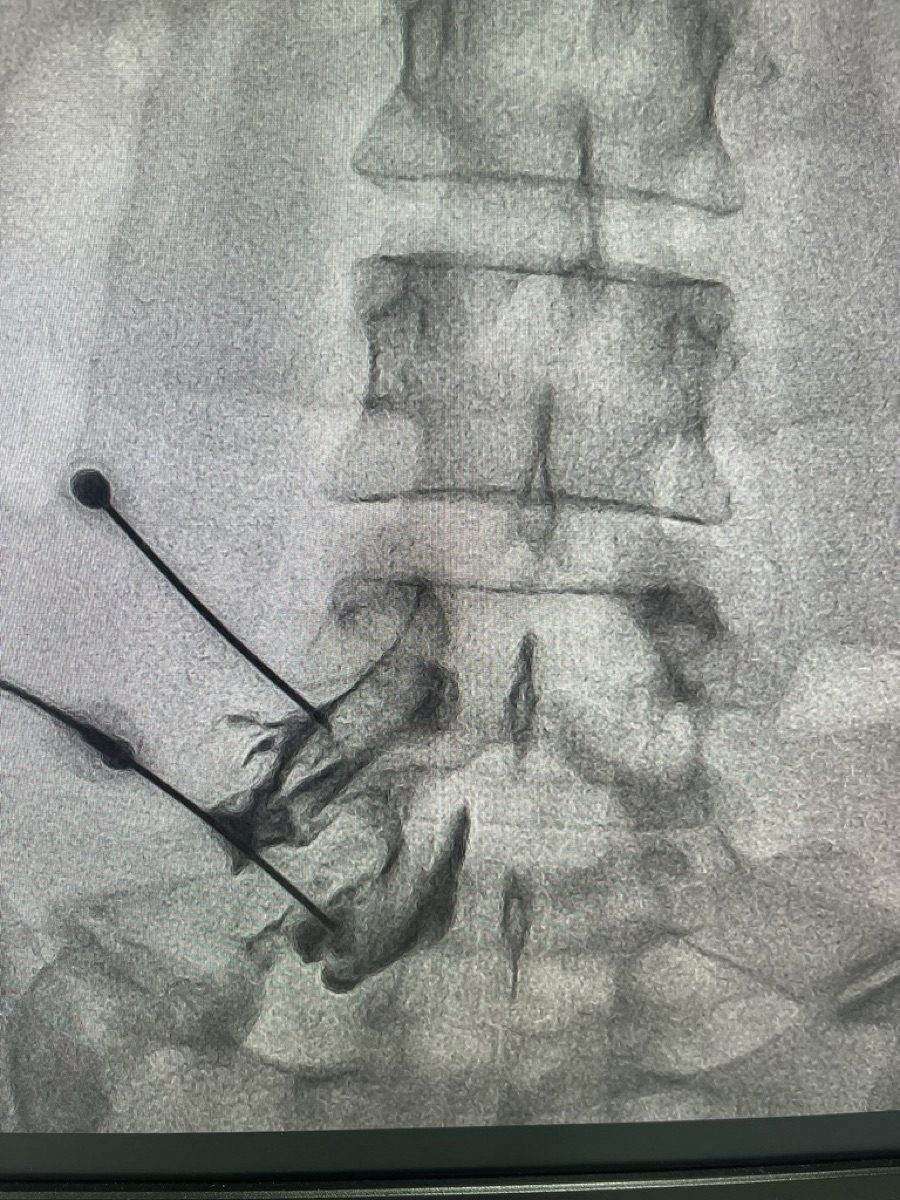

Epidural steroid injection being administered under fluoroscopic guidance

In these scenarios, a well-placed ESI - delivered under fluoroscopic guidance to the correct level and side - can produce dramatic relief. Multiple injections, spaced weeks apart, may be needed for sustained benefit.